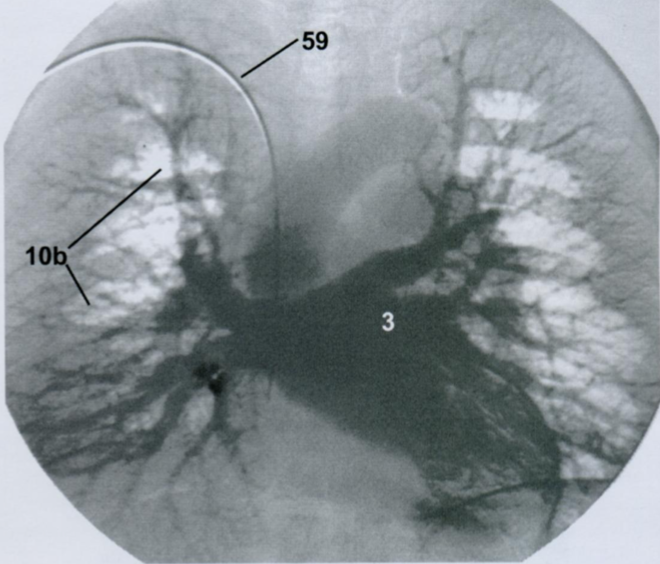

19

Q

Ангиографическая визуализация сосудов легких.

Какая фаза распространения контраста? Артериальная или венозная?

Назовите все пронумернованные структуры.

Ангиография выполняется с помощью введения контраста через катетер в полой вене, правом предсердии или артериях малого круга.

A

Венозная фаза. Норма.

3 - левое предсердие

10b - легочные вены

59 - катетер